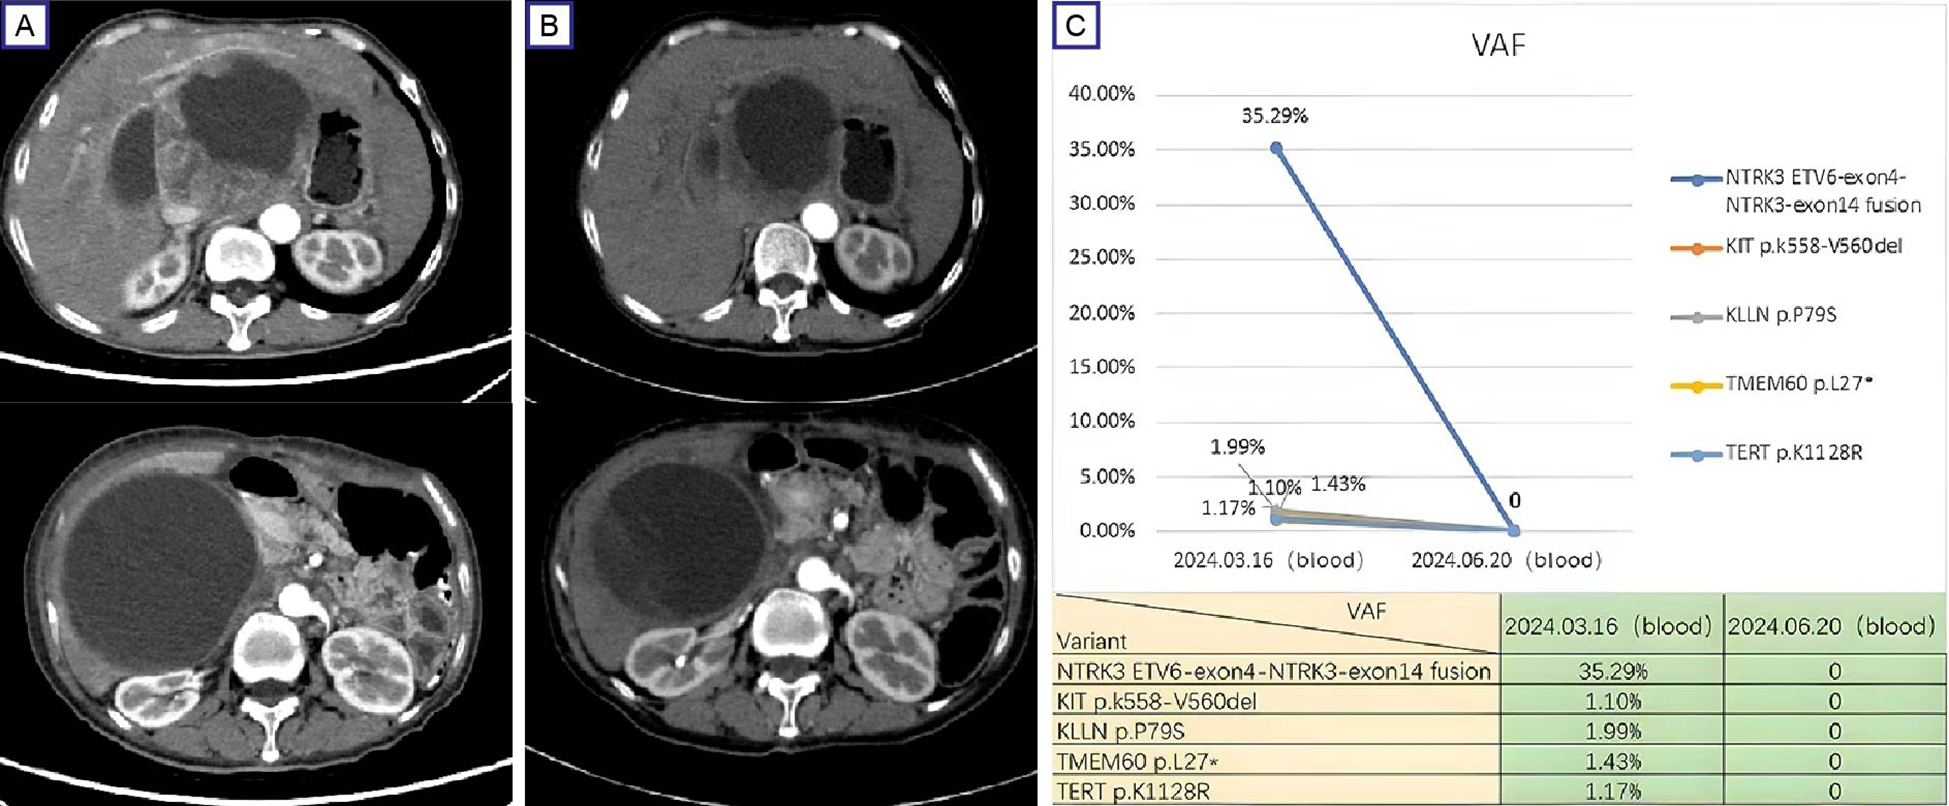

In March 2024, the patient returned to our hospital with recurrent abdominal distension. Contrast-enhanced CT revealed progressive GIST features include anastomotic soft-tissue thickening, cystic-solid masses and compression changes in the inferior vena cava (Figure 3A). As the disease progressed, the patient refused to undergo a repeat biopsy, and Plasma ctDNA analysis was performed after full communication with the family,Plasma ctDNA analysis identified the residual KIT mutation (VAF 1.10%) and an recurrent ETV6:NTRK3 fusion (ETV6 exon4:NTRK3 exon14; VAF 35.29%). Entrectinib therapy (600 mg daily) was initiated on March 28, 2024. Follow-up CT at 4 weeks demonstrated partial response (RECIST 1.1) (Figure 3B). Repeat ctDNA profiling in June 2024 confirmed complete clearance of both mutations (Figure 3C). The patient remained asymptomatic with sustained radiographic response at final telephone follow-up (October 31, 2024). So far, the patient was continuing entrectinib without reported adverse events.

Figure 3

Therapeutic response and mutation dynamics in progressive GIST. (A) Pre-treatment contrast-enhanced CT (March 28, 2024) demonstrates a dominant cystic-solid mass (12.6 cm×10.8 cm, arrows) in the hepatogastric space with IVC compression; (B) Post-treatment (entrectinib) contrast-enhanced CT (April 25, 2024) shows partial response (RECIST 1.1) with 27% tumor reduction (9.6 cm × 8.4 cm) and improved IVC compression. (C) ctDNA profiling reveals clearance of KIT exon 11 deletion (p.K558_V560del) and ETV6:NTRK3 fusion (ETV6 exon4:NTRK3 exon14) following entrectinib therapy. IVC, inferior vena cava.